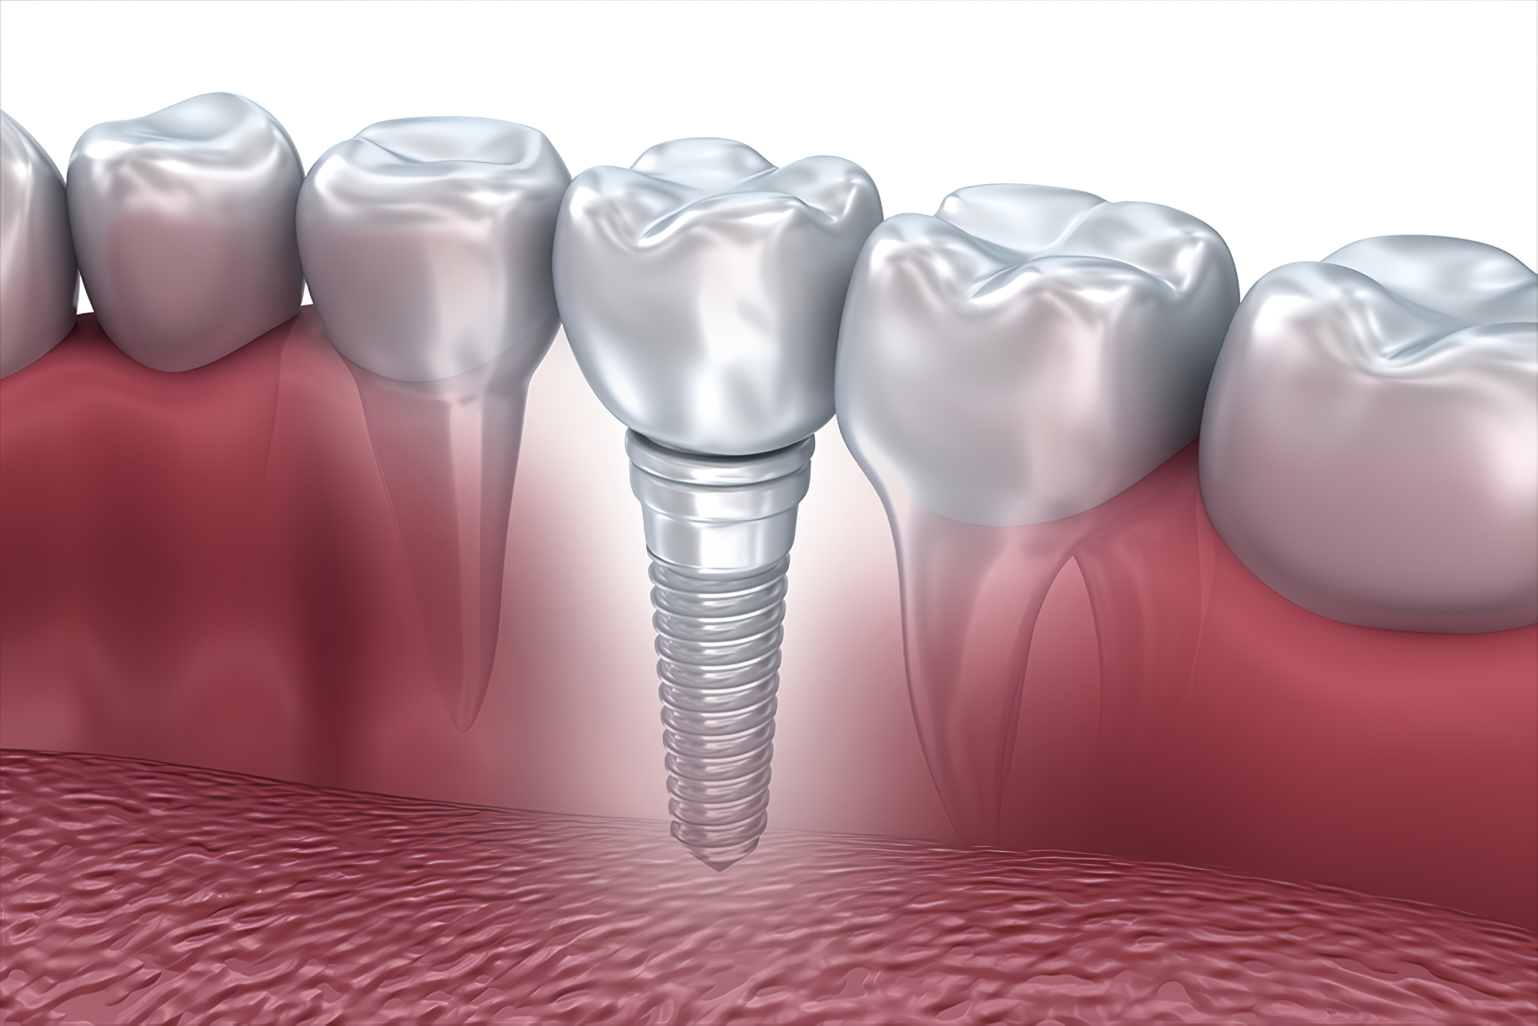

インプラントとは、あごの骨に人工の歯を埋め込む治療法です。顎の骨にしっかりと固定されるため、まるで天然歯のような感覚で使用できます。石井デンタルクリニックでは治療前にCT撮影を行い、骨の厚さや神経の位置を正確に把握して、安全なインプラント埋入計画を立てています。

手術後およそ6〜12週間で、埋め込んだインプラント体が顎の骨と結合します。この結合によって安定した支えが生まれ、しっかり噛める強固な人工歯が完成します。さらに、ブリッジのように周囲の健康な歯を削る必要がない点や、自然な見た目を再現できる点もインプラントの大きな特長です。

治療後のメンテナンスも重要で、天然歯と同様にインプラントも毎日の清掃が必要です。定期検診ではインプラント周囲のチェックとクリーニングを行い、長期的な機能維持をサポートします。インプラントは成功率が高く長持ちする治療ですが、持病や骨量の不足など個々の状態によって最適な治療法を検討します。ご不安な点があればお気軽にご相談ください。

しっかり噛める機能性と自然な見た目の両方を大切にしたい方には、インプラント治療の選択をおすすめします。院長は口腔外科も専門としていますので、難症例にも対応可能です。インプラント治療に伴うリスクや費用についても、わかりやすくご説明しています。